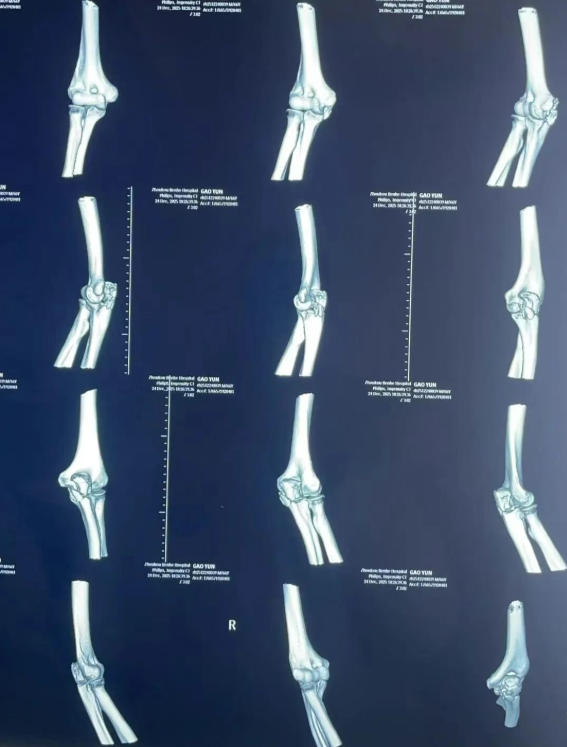

术前